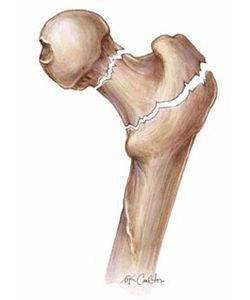

Η αντιμετώπιση της οστεοπόρωσης αποτελεί ακρογωνιαίο λίθο της δημόσιας υγείας αφού πρόκειται για μια συχνότατη πάθηση και οι επιπτώσεις καθώς και οι επιπλοκές της έχουν ιδιαίτερο κοινωνικο-οικονομικό αντίκτυπο στις οικογένειες των ασθενών, στο σύστημα υγείας και στην εθνική οικονομία.Η κύρια κλινική εκδήλωση της οστεοπόρωσης είναι τα κατάγματα ευθρυπτότητας (χαμηλής ενέργειας), κατάγματα που συμβαίνουν μετά από ελαφρού βαθμού τραυματισμό, όπως είναι η πτώση από την όρθια θέση. Περίπου στο 40% των περιπτώσεων τα οστεοπορωτικά κατάγματα αφορούν τους σπονδύλους, 20% τον αυχένα του μηριαίου οστού, 20% την κερκίδα και 20% διάφορα άλλα οστά. Αν και η οστεοπόρωση γενικά θεωρείται ως πάθηση των γυναικών, ωστόσο, όπως ήδη αναφέρθηκε παραπάνω, η οστεοπόρωση προσβάλλει και τους άνδρες.

Η οστεοπόρωση είναι μια σιωπηρή νόσος, δεν παρουσιάζει συμπτώματα για μεγάλο χρονικό διάστημα. Αυτό σημαίνει ότι περνάνε αρκετά χρόνια, κατά τη διάρκεια των οποίων η οστεοπόρωση συνεχώς χειροτερεύει από πλευράς απώλειας οστικής μάζας και διαταραχής της μικροαρχιτεκτονικής δομής των οστών, μέχρι να εμφανιστεί το πρώτο της σύμπτωμα, που είναι το κάταγμα. Η οστεοπόρωση είναι νόσος όλων των οστών και γι’ αυτό κατάγματα μπορεί να συμβούν σε διάφορες θέσεις του σκελετού, αλλά συνήθως συμβαίνουν στους σπονδύλους, στον αυχένα του μηριαίου οστού και στο αντιβράχιο. Πιο συγκεκριμένα, περίπου 40% των οστεοπορωτικών καταγμάτων αφορούν τη σπονδυλική στήλη, 20% τον αυχένα του μηριαίου οστού, 20% το αντιβράχιο και 20% διάφορα άλλα οστά. Τα κατάγματα του αυχένα του μηριαίου οστού και του αντιβραχίου συμβαίνουν πάντοτε μετά από έναν χαμηλής βίας τραυματισμό, όπως είναι η πτώση από την όρθια θέση, ενώ συνοδεύονται πάντοτε από πόνο. Αντίθετα, τα σπονδυλικά κατάγματα συμβαίνουν συχνά χωρίς να προηγηθεί τραυματισμός και αρκετές φορές δεν συνοδεύονται από πόνο στη ράχη ή στη μέση παρά μονάχα από ένα ελαφρύ αίσθημα καύσου. Απώλεια ύψους και κύφωση αποτελούν όψιμες εκδηλώσεις της οστεοπόρωσης και οφείλονται σε σπονδυλικά κατάγματα.